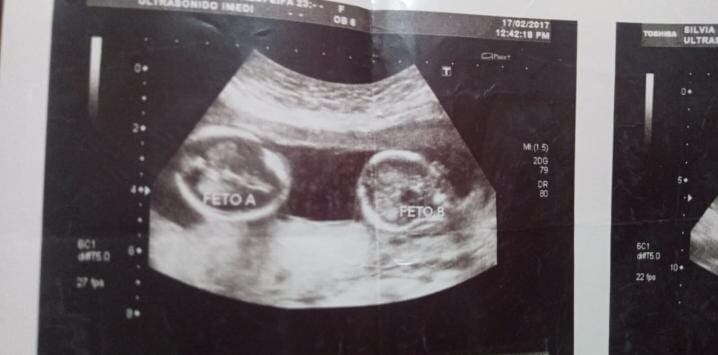

No solo confirmó su embarazo de aproximadamente cuatro meses, sino que tendría gemelas, las cuales actualmente tienen cuatro años.

“Para mí fue un shock, fue un baño de agua fría. Empezaron a surgirme las preguntas sobre qué iba a hacer. Pero desde que las vi en la pantalla (del ultrasonido) fue un borrón y cuenta nueva y dejé atrás todas las ideas que tenía de no tener ese embarazo. Pensé que tenía a dos personas más por las cuales luchar y amar. También pensé que ellas me ayudarían a sanar mis heridas. A partir de ese momento Ifemsi se convirtió en mi segunda familia, en los ángeles de mi vida y de mis hijas”, agregó Silvia, de 28 años.